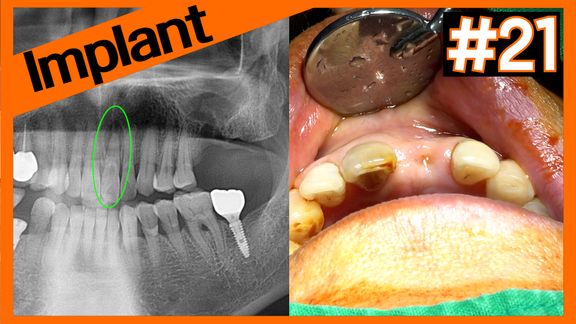

2 stage implant on #21 after socket preservation using A-Oss Collagen

2 stage implant on #21 after socket preservation using A-...

Online Surgery

Просмотры 41